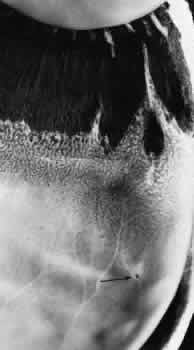

Fig. 12. Enclosed ora bay in a 35-year-old man. Anteriorly, two broad dentate processes converge and join to enclose a bay (island of pars plana). Posteriorly there is a focus of retinal thinning (peripheral retinal excavation; arrow). (× 12.)

PERIPHERAL RETINAL EXCAVATION

Peripheral retinal excavation appears as a rather small oval depression in the retina. Usually this lesion is aligned meridionally with a meridional fold or complex and located 1 to 7.2 mm posterior to the ora serrata (Fig. 13; see Figs. 6 and 12). The focal depression may be surrounded by margins that appear to be elevated; however, microscopic examination reveals that the depression corresponds to afocal loss of the inner retinal layers and that the surrounding tissue is normal (Fig. 14).

Fig. 13. Meridional complexes with peripheral retinal excavation. Two complexes can be seen anteriorly; both contain meridional folds (the fold of complex on the right is discontinuous). Peripheral retinal excavation (arrow) is aligned with the complex on the left (× 12.)